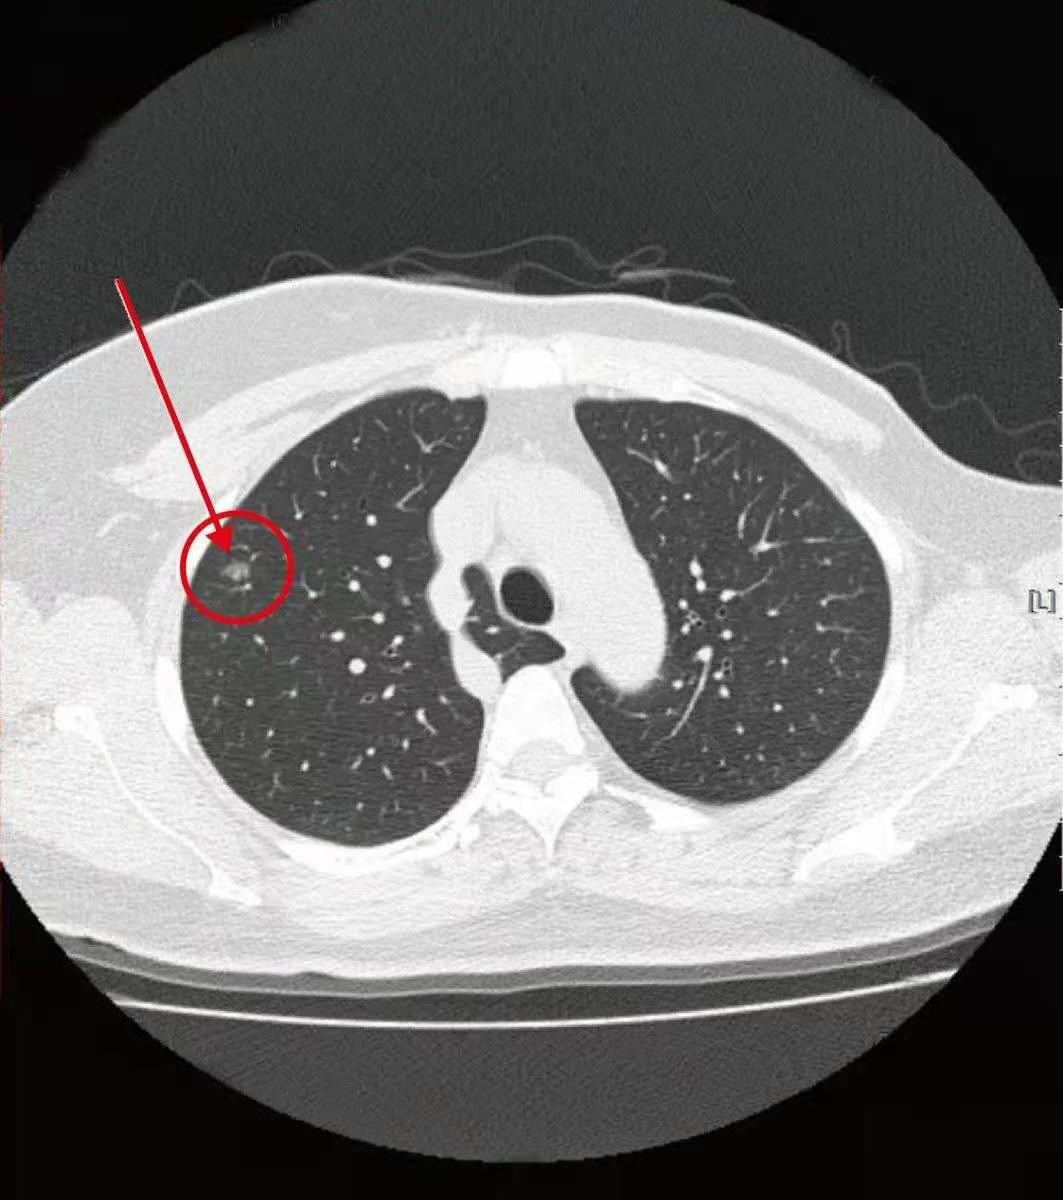

我认真看了她的肺结节,位于右肺下叶,直径约1厘米,属于混杂密度磨